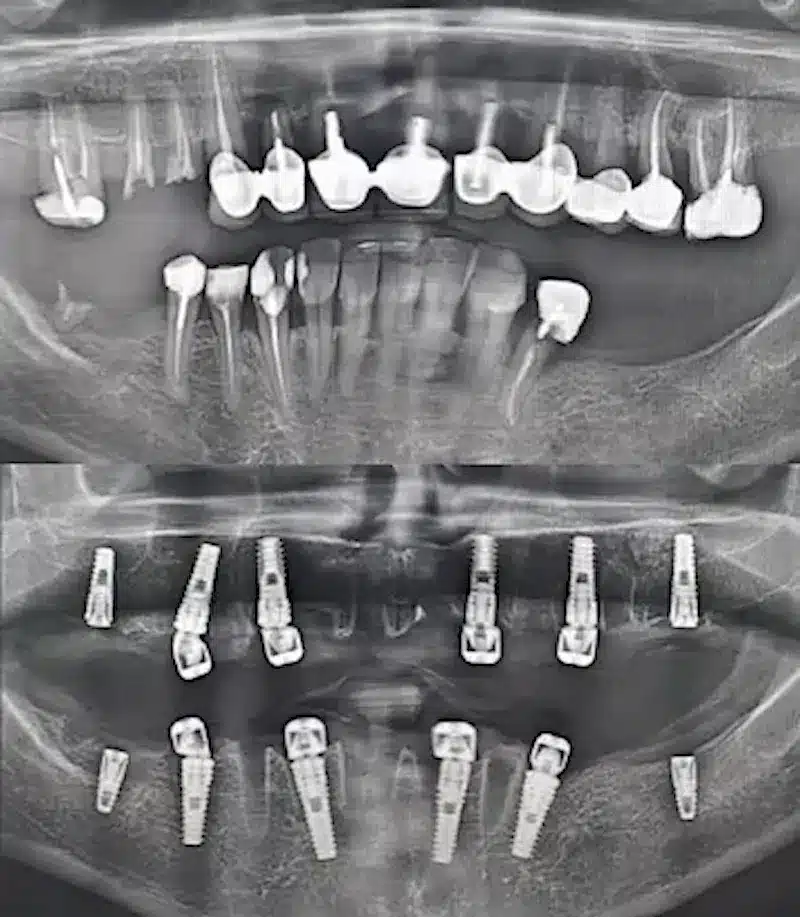

Dr. Seden Aksu is a specialist in modern implantology and surgical dentistry with extensive experience in the management of complex clinical cases. In her practice, she applies comprehensive surgical planning, minimally invasive techniques, and advanced regenerative technologies aimed at restoring both the function of the dentoalveolar system and the aesthetics of the smile. Dr. Aksu has significant experience in performing implant procedures, bone augmentation, and periodontal surgery, including the treatment of patients with severe bone loss. The primary goal of her work is to achieve stable, long-term outcomes in implant rehabilitation and the restoration of oral tissue health.